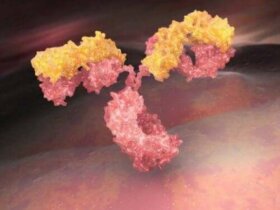

나노 기술은 주로 1미크론보다 더 작은 크기로 어떤 물질을 조작하고 제어하는 기술이다. 어떤 물질과 시스템을 만드는 데 모든 기능을 수행할 수 있다. 나노 기술 발전과 더불어 나노의학의 발전은 질병의 예방, 진단 및 치료에 관한 건강 과학에 기여했다. 나노의학은 건강한 조직은 손상시키지…